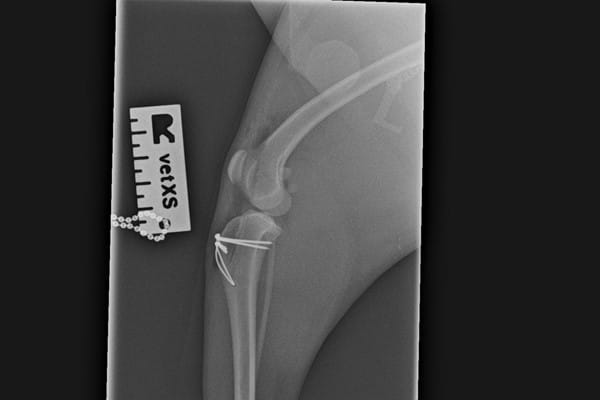

He discussed his findings with Sally and advised x-rays to further investigate the issue. The x-rays showed that Margaret had some inward deviation of her shin-bones which had happened whilst she was still growing and this was contributing to the laxity. Dr. Higson advised surgical correction for both of Margaret's hind legs, as the looseness of the kneecaps was causing discomfort and joint arthritis. Surgery was scheduled for the first leg and during the procedure, Dr. Higson deepened the groove the patella runs in and corrected the angulation of the top of the shin-bone.